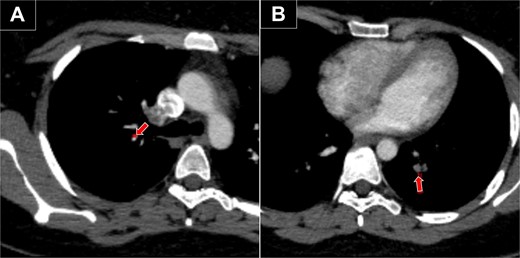

A 45-year-old woman with a history of anemia and a BMI of 20.1 kg/m2 presented with lipodystrophy of the abdomen, outer thighs, and inner knees. She was preoperatively evaluated and received an ASA I. Third-generation ultrasound-assisted liposuction, VASER (Sound Surgical Technologies, Colorado, USA), was performed under general anesthesia. Subcutaneous infiltration consisted of 1000 ml isotonic saline and 1 ml epinephrine 1/1000 infiltrated into the aforementioned lipodystrophic areas. Ultrasound was applied with a 3.7 mm probe at 80% amplitude in continuous mode. After emulsification, 1000 ml of fat and fluid were removed by traditional liposuction. The operative time was 130 min, and graduated compression stockings were used. On postoperative Day 6, the patient presented with respiratory distress, with an oxygen saturation of 96% and a heart rate of 105 bpm. Doppler ultrasound of the lower extremities showed no evidence of DVT, while chest tomography revealed bilateral PE (Fig. 1).

Chest CT with bilateral PE. (A) Embolism in the segmental artery of the right upper lobe (arrow). (B) Embolism in the posterior segmental artery of the left lower lobe (arrow).